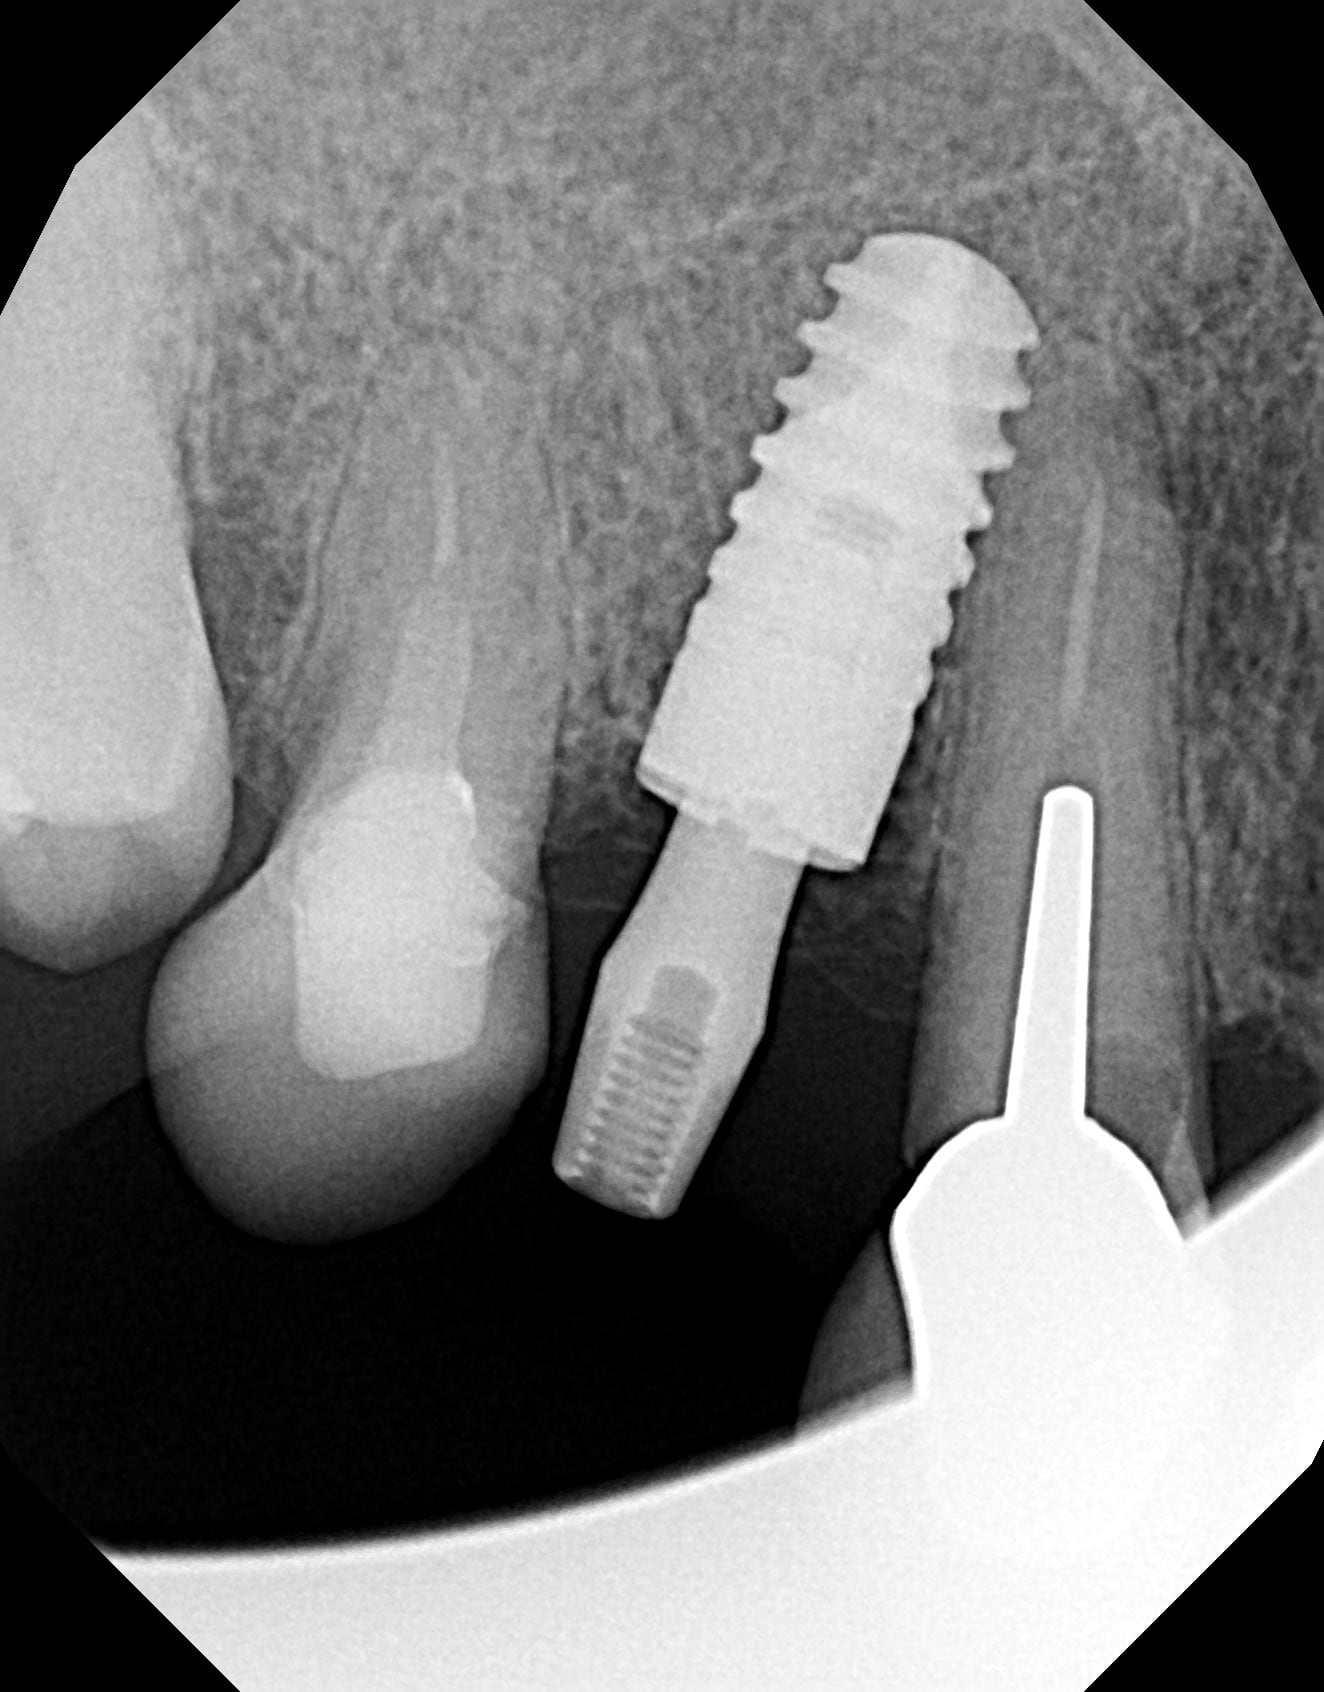

Bonjour, je cherche à identifier un implant qui me semble être un ANKYLOS mais quel modèle ?

Ankylos, oui certain, 100%